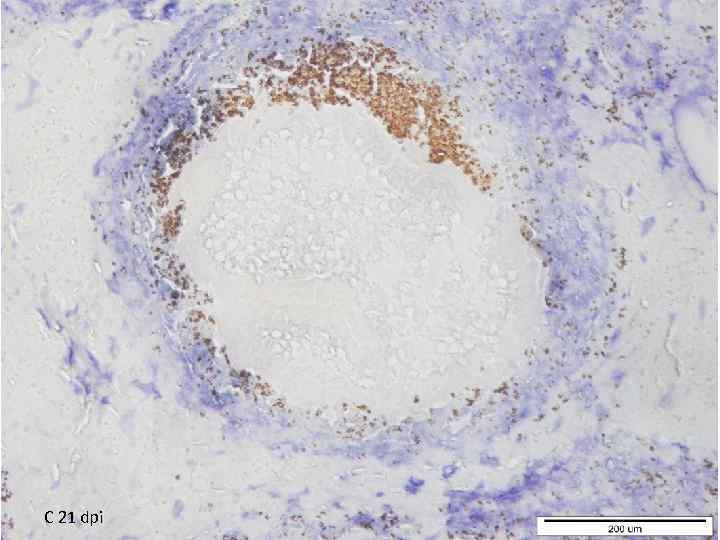

C 21 dpi